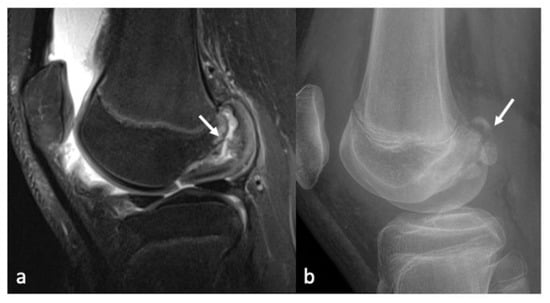

- Gorbachova, T.; Melenevsky, Y.; Cohen, M.; Cerniglia, B.W. Osteochondral Lesions of the Knee: Differentiating the Most Common Entities at MRI. Radiographics 2018, 38, 1478–1495. [Google Scholar] [CrossRef]

- Berndt Al Harty, M. Transchondral fractures (osteochondritis dissecans) of the talus. J. Bone Jt. Surg. Am. 1959, 41, 988–1020. [Google Scholar] [CrossRef]

- Anderson, I.F.; Crichton, K.J.; Grattan-Smith, T.; Cooper, R.A.; Brazier, D. Osteochondral fractures of the dome of the talus. J. Bone Jt. Surg. Am. 1989, 71, 1143–1152. [Google Scholar] [CrossRef]

- Loomer, R.; Fisher, C.; Lloyd-Smith, R.; Sisler, J.; Cooney, T. Osteochondral lesions of the talus. Am. J. Sport. Med. 1993, 21, 13–19. [Google Scholar] [CrossRef]

- Hepple, S.; Winson, I.G.; Glew, D. Osteochondral Lesions of the Talus: A Revised Classification. Foot Ankle Int. 1999, 20, 789–793. [Google Scholar] [CrossRef]